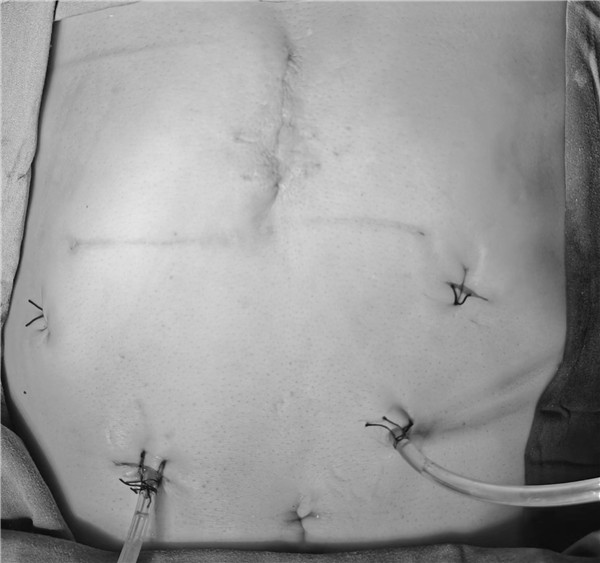

经过周密的术前准备、评估和充分的医患沟通后,由普通外科陆宏伟教授主刀,卢乐主治医师和尚皓助理研究员担任助手,在麻醉手术科雷晓明主任医师、赵丽燕护士长团队的保驾护航和和精密配合下,为奥先生实施了全腹腔镜下胰十二指肠切除手术。术中情况与手术术前评估高度吻合,术中暴露良好,手术减创而不减质,在充分清扫淋巴结的同时完整保护了重要脉管,手术历时8小时,术中出血100mL。